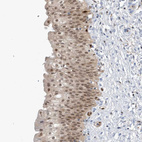

Immunohistochemical staining of human urinary bladder shows moderate nuclear positivity in urothelial cells.